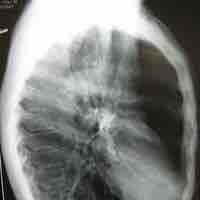

Lung development can be divided into distinct stages: the pseudoglandular period, the canalicular period, and the terminal saccular period.

In mammals, breathing in is due to a flattening of the diaphragm and lung expansion. Lung elasticity declines with aging.